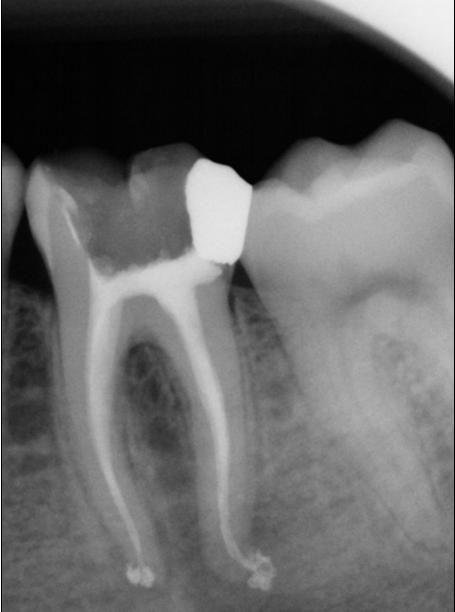

Di seguito sono state inserite le radiografie finali di altrettanti denti devitalizzati, omettendo le radiografie eseguite all’inizio e durante la cura canalare, per avere la possibilità di una più ampia carrellata di casi. Le devitalizzazioni sono state eseguite secondo la tecnica della condensazione verticale con onda di calore. Sono stati scelti denti che presentassero qualche piccola particolarità come radici particolarmente curve, doppi canali, delta apicale molto diramato, ecc. Tutti i casi riportati sono stati eseguiti personalmente dal dr Michele Caruso. E’ importante notare che l’obiettivo principale della cura canalare è la sigillatura dell’apice dentale. Questo risultato si ottiene, in modo tridimensionale ed ermetico, con una ottima sagomatura e detersione dei canali che devono essere stati preparati sotto diga di gomma e a bagno di ipoclorito di sodio al 5% per un’ora. Prima della asciugatura finale, i canali radicolari vanno riempiti di ipoclorito e va inserito all’interno di essi fino a 2 mm. dall’apice un K-file da 10 montato su manipolo da ultrasuoni, al fine di eliminare gli ultimi residui organici. Questa operazione va ripetuta alcune volte finchè l’ipoclorito non resta completamente limpido anche sotto l’azione degli ultrasuoni. L'apice va quindi sigillato con guttaperca appena sporcata di cemento canalare e scaldata per compattarla secondo la tecnica della condensazione verticale. Solo in questo modo si potrà evitare la comparsa di un granuloma apicale o, se presente, farlo guarire. Lo “sbuffetto” di gomma appena oltre apice è un segno assolutamente benigno ed è garanzia, quando è stata seguita una corretta procedura, di sigillo apicale.